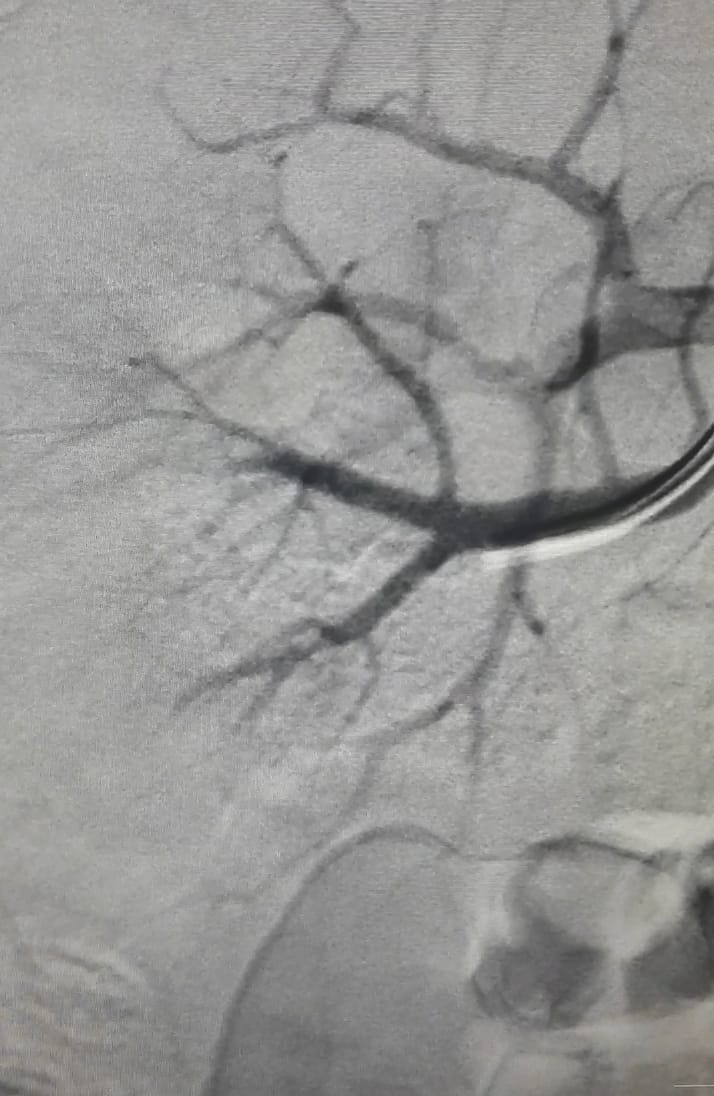

Хирургические процессы при эмболизации гемангиомы на фото

Раздел: Снимки-откровения